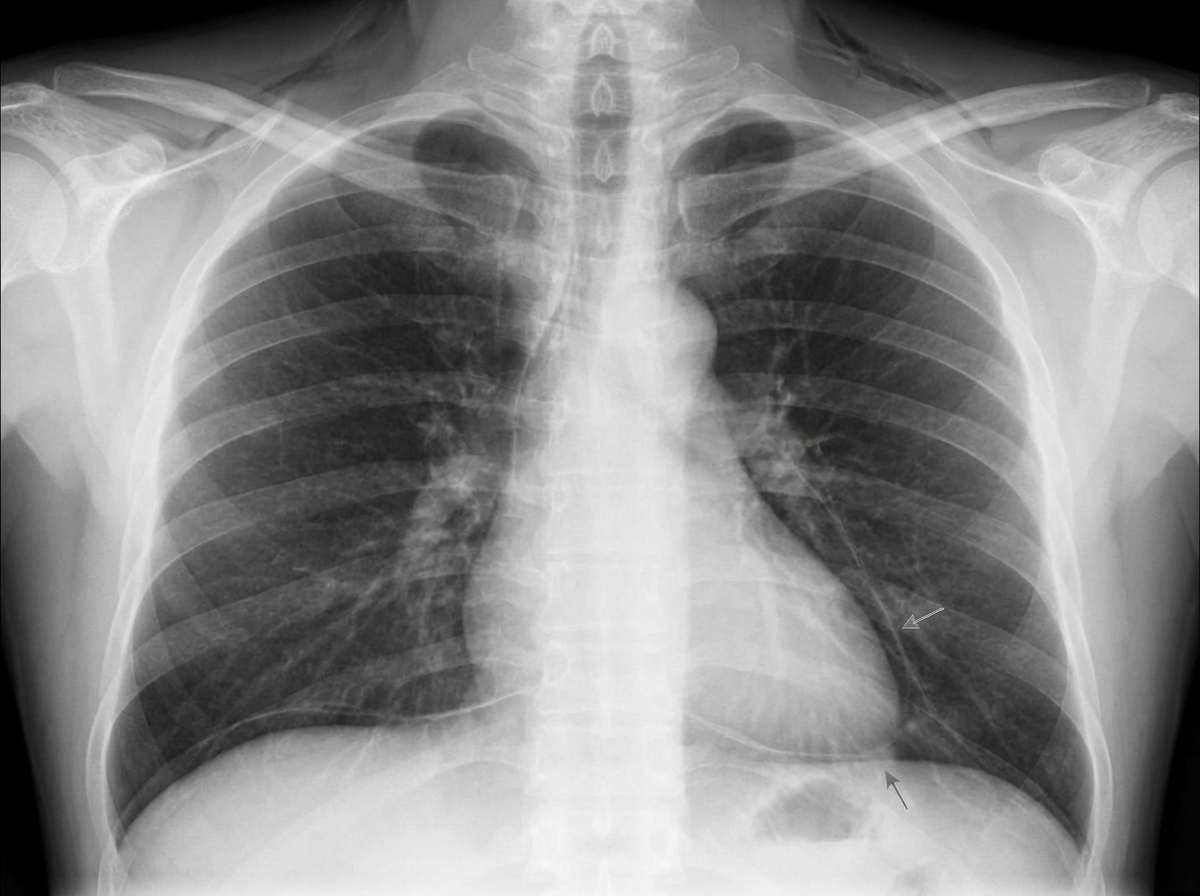

A 17-year-old boy presents to the emergency department for the evaluation of severe chest pain that started one hour ago. The pain suddenly began after he lifted a heavy object and the pain is constant. He has no history of a serious illness and takes no medications. His blood pressure is 125/85 mm Hg, the pulse is 89/min, the respiratory rate is 15/min, and the temperature is 36.7°C (98.1°F). Examination of the supraclavicular notch shows mild swelling of the skin with crepitation on palpation. Auscultation of the precordium in the left lateral decubitus position reveals a clicking sound with every heartbeat. The remainder of the physical examination shows no abnormalities. A chest X-ray is shown. Which of the following is the most appropriate next step in management?